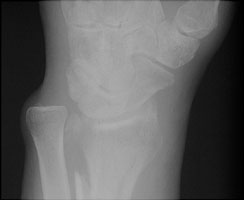

- Click on the image for a larger versionAPA radiograph of the wrist. There is irregularity of the distal radial margin. In addition, a fracture of the distal radius is appreciated.